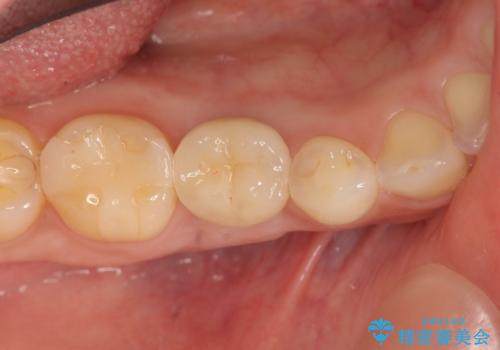

- 40万円(ストローマンインプラント・カスタムジルコニアアバットメント・ジルコニアクラウン)費用は治療当時の料金となります

大人になっても残っている乳歯は根管治療や他の治療で残せる場合もありますが、今回のように状態が悪い場合早期に抜歯をすることで歯槽骨が温存でき十分に安定した骨量でインプラントによる機能回復を達成することができました。